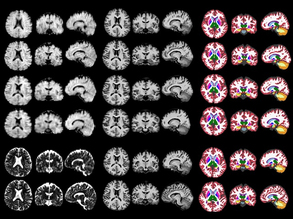

Virtual Pathologist